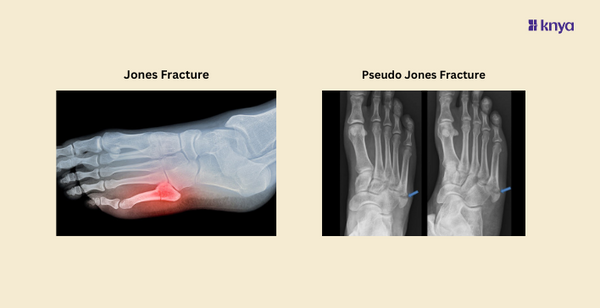

A pseudo Jones fracture, also known as an avulsion fracture of the fifth metatarsal, occurs at a different location on the bone compared to a true Jones fracture. This type of fracture typically involves the tuberosity or styloid process of the fifth metatarsal, which is located more proximally (closer to the midfoot) than the base of the bone.

Diagnosing a pseudo Jones fracture also involves a physical examination and imaging studies, typically X-rays. On X-ray, this type of fracture appears as a fragment or avulsion of the tuberosity of the fifth metatarsal, often with displacement or separation from the main bone.